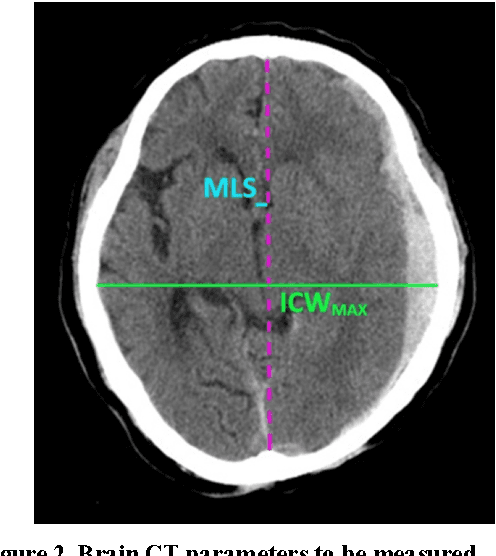

Abstract:Brain CT has become a standard imaging tool for emergent evaluation of brain condition, and measurement of midline shift (MLS) is one of the most important features to address for brain CT assessment. We present a simple method to estimate MLS and propose a new alternative parameter to MLS: the ratio of MLS over the maximal width of intracranial region (MLS/ICWMAX). Three neurosurgeons and our automated system were asked to measure MLS and MLS/ICWMAX in the same sets of axial CT images obtained from 41 patients admitted to ICU under neurosurgical service. A weighted midline (WML) was plotted based on individual pixel intensities, with higher weighted given to the darker portions. The MLS could then be measured as the distance between the WML and ideal midline (IML) near the foramen of Monro. The average processing time to output an automatic MLS measurement was around 10 seconds. Our automated system achieved an overall accuracy of 90.24% when the CT images were calibrated automatically, and performed better when the calibrations of head rotation were done manually (accuracy: 92.68%). MLS/ICWMAX and MLS both gave results in same confusion matrices and produced similar ROC curve results. We demonstrated a simple, fast and accurate automated system of MLS measurement and introduced a new parameter (MLS/ICWMAX) as a good alternative to MLS in terms of estimating the degree of brain deformation, especially when non-DICOM images (e.g. JPEG) are more easily accessed.